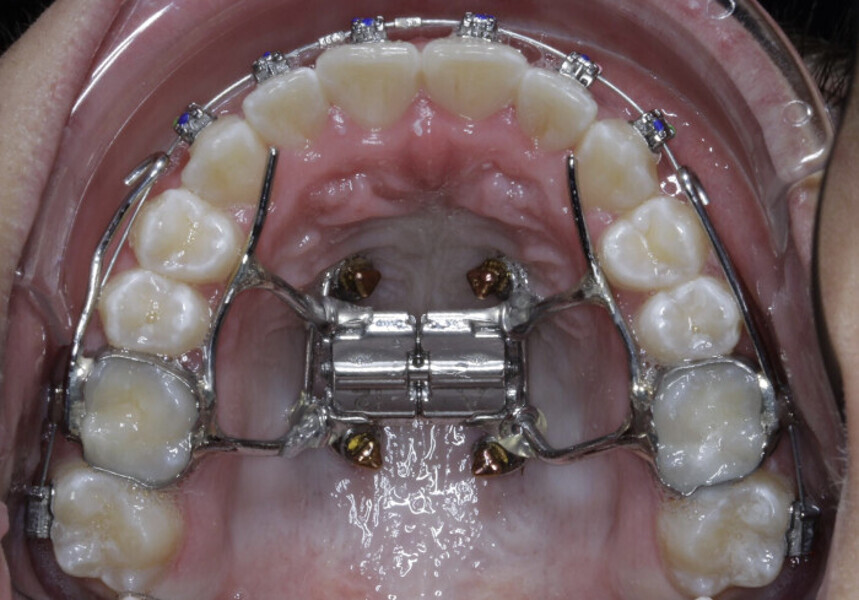

New Age orthodontics and orthopaedics with temporary anchorage devices